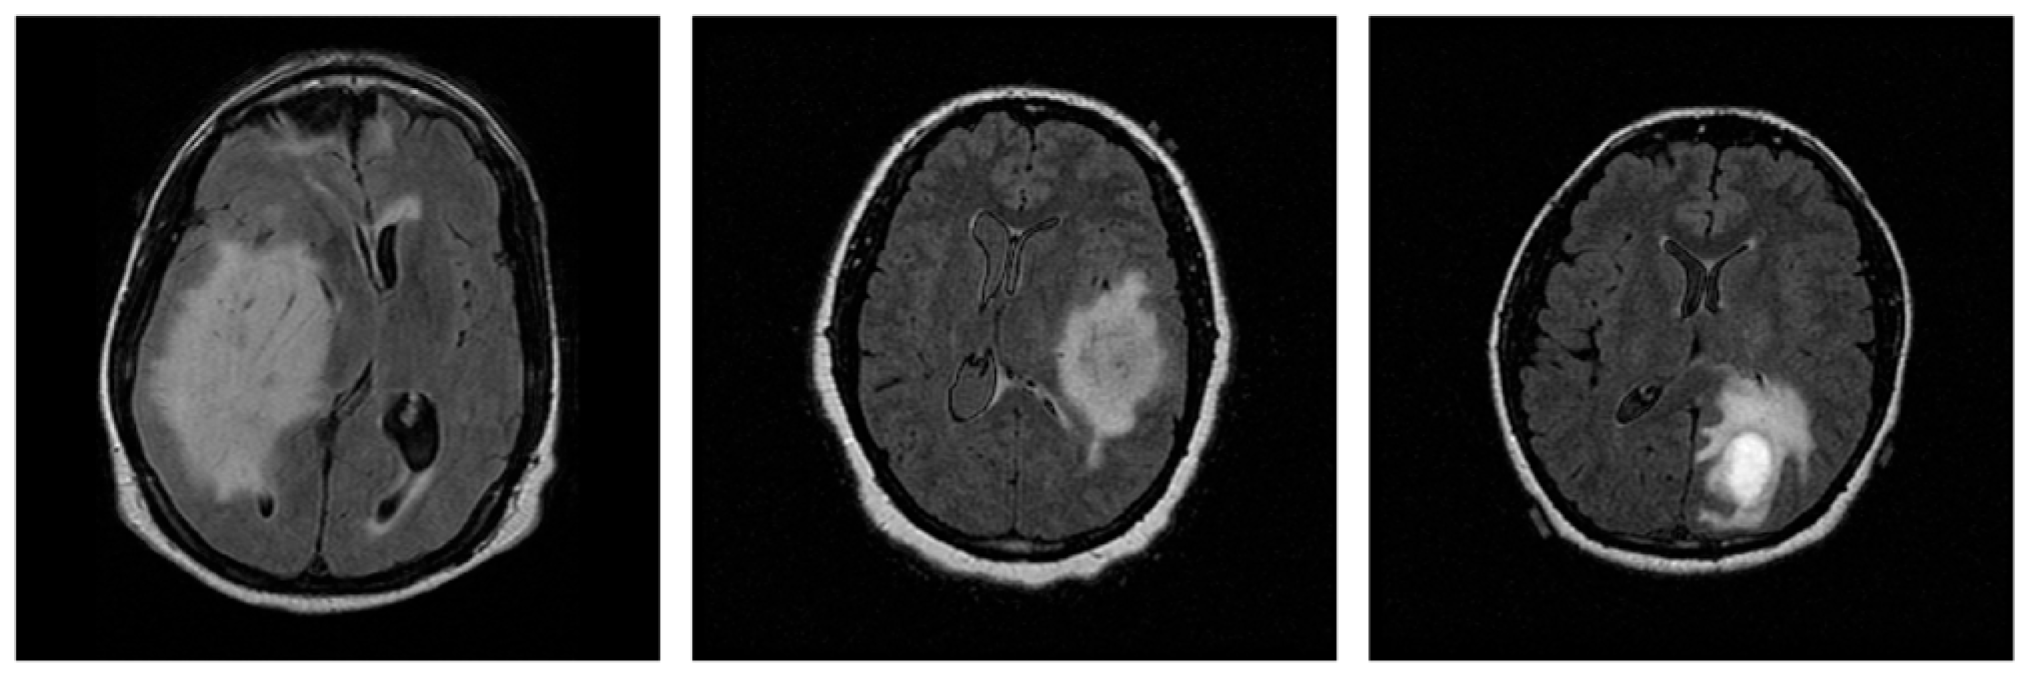

In medical imaging, including MRI scans, various sources of variation, such as artifacts caused by patient movement or acquisition inconsistencies, can affect image quality and, consequently, diagnostic assessments. These factors underscore the importance of evaluating the robustness of the proposed CNN under realistic perturbations, in addition to its generalization capabilities. For this purpose, mild geometry-based augmentations were applied exclusively to the training set, with each original slice replaced by a single augmented version, thereby ensuring that no augmented slice appeared in the test set, while simulating potential variability in real-world data. Specifically, random translations were performed by shifting the image up to 0.25% of its width or height, while random zoom operations were performed within a ±1% range. Additionally, random rotations were introduced, in 5% of a full cycle, corresponding to angular shifts of ±18 degrees. These augmentation parameters were configured within a safe and widely adopted range, as suggested in the literature [25,26], ensuring the preservation of diagnostic information, while evaluating the model’s performance under spatial variability. Figure 4 displays five original sample slices alongside their augmented counterparts, generated using random rotation, flipping, and shifting.

Figure 4. Representative original MRI slices from the training set (top row) and their corresponding augmented versions (bottom row), generated using random rotation, flipping, and shifting.